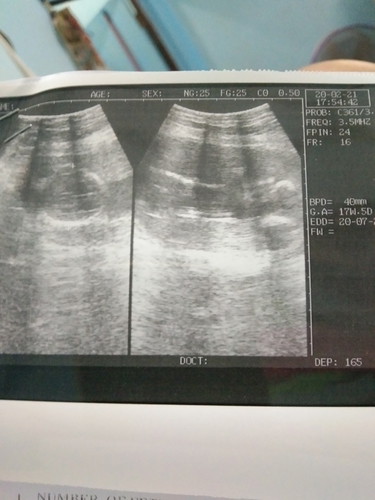

หลังจากที่หมอสองคนเถียงกันเรื่องอายุครรภ์ สรุปตั้งครรภ์ได้ 17 สัปดาห์ 4 วัน แล้วค่ะ หมอคนแรกบอกตั้งครรภ์ได้ 9 สัปดาห์ เราก็ งง! พอซาวด์ก็ได้รู้อายุครรภ์จริงๆ??? อีกไม่กี่เดือนก็ได้เจอกันแล้ว???